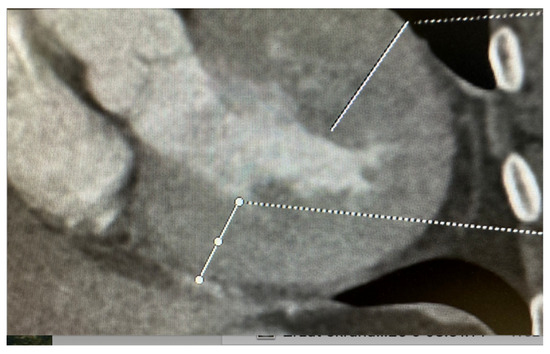

2.3. Computed Tomography: A Complementary Modality